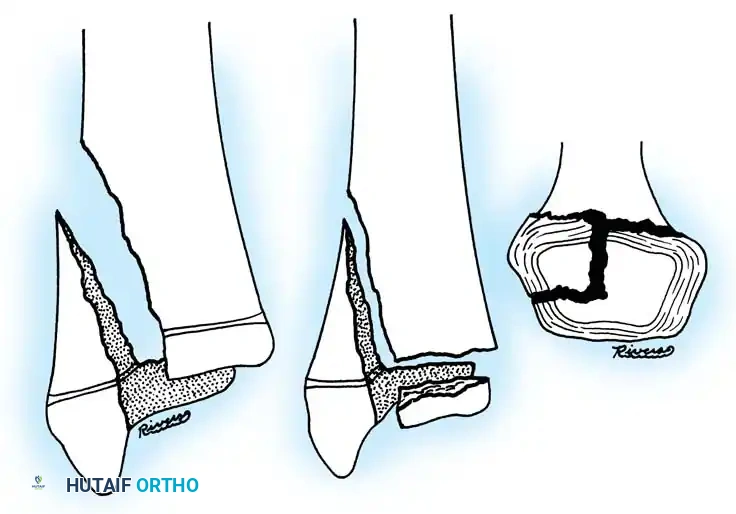

Fig. 33-174: Salter-Harris type III fracture of the proximal tibia. A, Fracture analogous to a tibial plateau fracture. B, Fracture through the tibial tuberosity and across the epiphysis into the knee joint.

These tuberosity-extending fractures are not simple avulsions; they are massive, tongue-type Salter-Harris III injuries that lift the entire tibial tuberosity and anterior proximal physis superiorly. They almost universally necessitate open reduction and internal fixation (ORIF) to restore joint congruity and extensor mechanism continuity.

- Type III Fractures: These present in two distinct patterns:

- An intra-articular fracture analogous to an adult tibial plateau fracture.

- A fracture propagating through the tibial tuberosity physis, extending proximally across the epiphysis and into the knee joint.